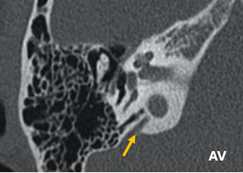

Acueducto vestibular (AV) y acueducto coclear (AC).

Se debe identificar la permeabilidad y dilatación. Se considera dilatación del AV cuando tiene un diámetro superior a 1,5 mm en el punto medio de su trayecto o mayor a 2mm en el opérculo. Así mismo se debe de valorar la permeabilidad y dilatación del AC, teniendo en cuenta que su diámetro habitual es de alrededor de medio milímetro en su apertura interna y de casi 3 mm en la apertura externa, su longitud es de unos 12 mm. Esta estructura tiene menor relevancia clínica que el AV. Sin embargo, ambos se han relacionado, aunque sin una evidencia fuerte, que pueden predisponer a presentar en la cirugía de estapedectomía o estapedotomía una salida abrupta de líquido cefalorraquídeo junto con líquido perilinfático conocido como Gusher o un Oozer y estos pueden conllevar a una hipoacusia neurosensorial postoperatoria (Fig. 8).

Figura 8. Acueducto coclear (AC) y Acueducto vestibular (AV) |